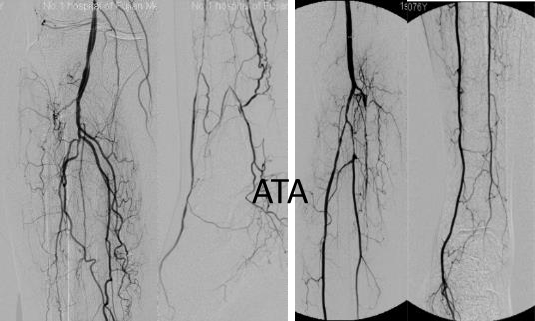

各分支 CTO 解剖特点

三大主要分支的CTO近端与远端常见位置:

总体特点:

膝下通常有单个或数个可见的流入道;

病变常为单个或多个CTO组合,总长度可达20cm;

部分患者存在踝上交通动脉或完整的踝下足底弓,为逆向开通提供可能。